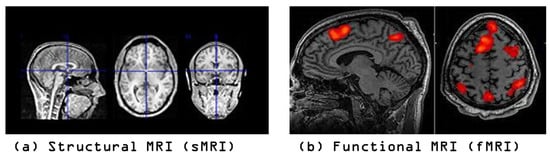

- Extracting 1, 10, and 50 slices along each brain plane (axial, sagittal, and coronal) to generate sequences of 2D images from raw 3D sMRI scans.

- Extracting 10, 30, and 50 slices along all brain planes (axial, sagittal, and coronal) to generate sequences of 3D images from raw 4D fMRI scans.

- Extracting all slices or giving some exceptions to the beginnings and the ends along all brain planes (axial, sagittal, and coronal) to generate sequences of 3D images from 3D sMRI and 4D fMRI scans.

- The study explores the diagnostic capability of the proposed 3D-CNN model to automatically leverage ASD biomarkers from 3D sMRI and fMRI generated data, and the classifiability of ASD subjects versus typical control (TC) subjects.